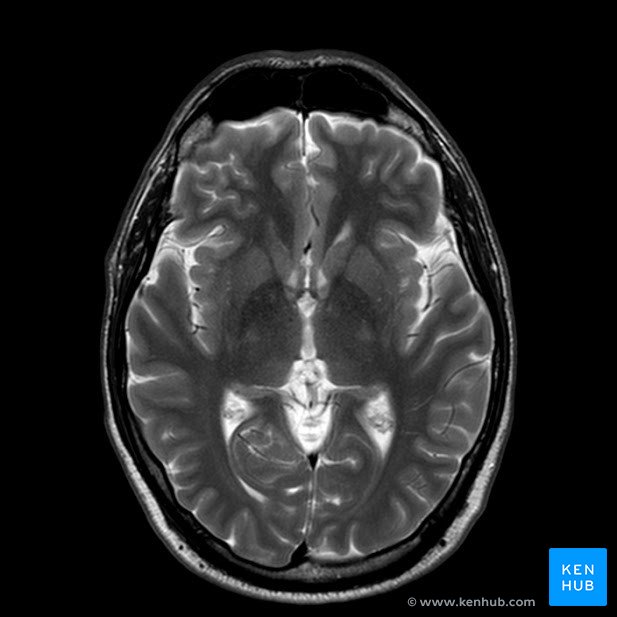

Specific Body MRIs

Get a specific body, organ, looked at with advanced MRI imaging

Partial body MRI for scanning of places such as abdomen, chest, or head.